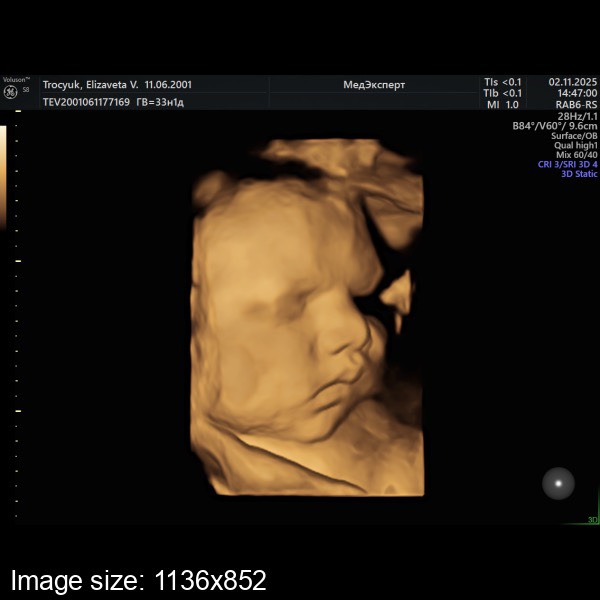

3 скрининг💓💓💓

Мы снова богатырши, и по фото копия сестрички 🥹🥹🥹

2670 вес🤭

Первая дочь в 34 недели весила 2999 родилась 4190, я думаю эта все ж будет больше🤭